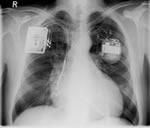

Dr. med. St. Steiner, Chefarzt, Rhythmologie Helios Kliniken Kassel

Die ICD-Therapie Licht ohne Schatten?